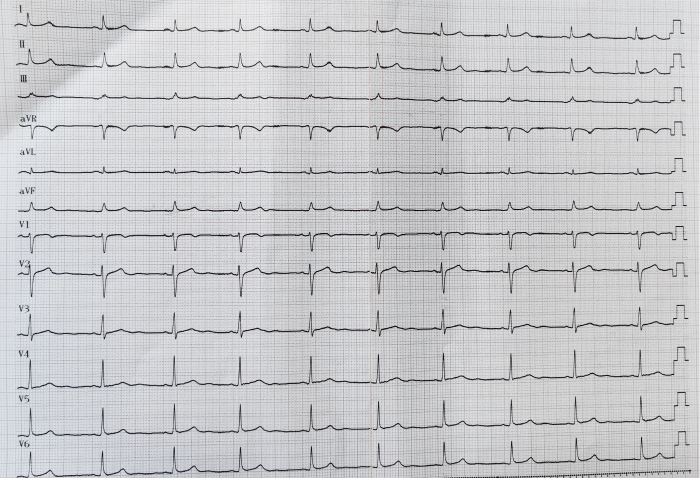

10月28日,周先生在中南大学湘雅二医院桂林医院(国家区域医疗中心)健康管理中心体检时,再次感到心悸、头晕,通过心电图检查发现患者是心律失常-频发短阵室性心动过速、偶发室早、窦性心动过缓。

患者术前心电图

11月1日,刘启明教授与湘雅二医院桂林医院心内科副主任赵印平在局部麻醉下为患者进行手术。周先生为右室流出道室早、室速,在三尖瓣瓣上、瓣下均有异位节律点,射频消融存在一定难度,极其考验施术者的手法。刘启明教授在不到两小时的时间就顺利完成手术,术后患者立即恢复窦性心律,于11月3日康复出院。周先生和家属感激地说:“感谢国家的好政策,感谢国家区域医疗中心,才有国内知名教授来桂林给我们做手术!”